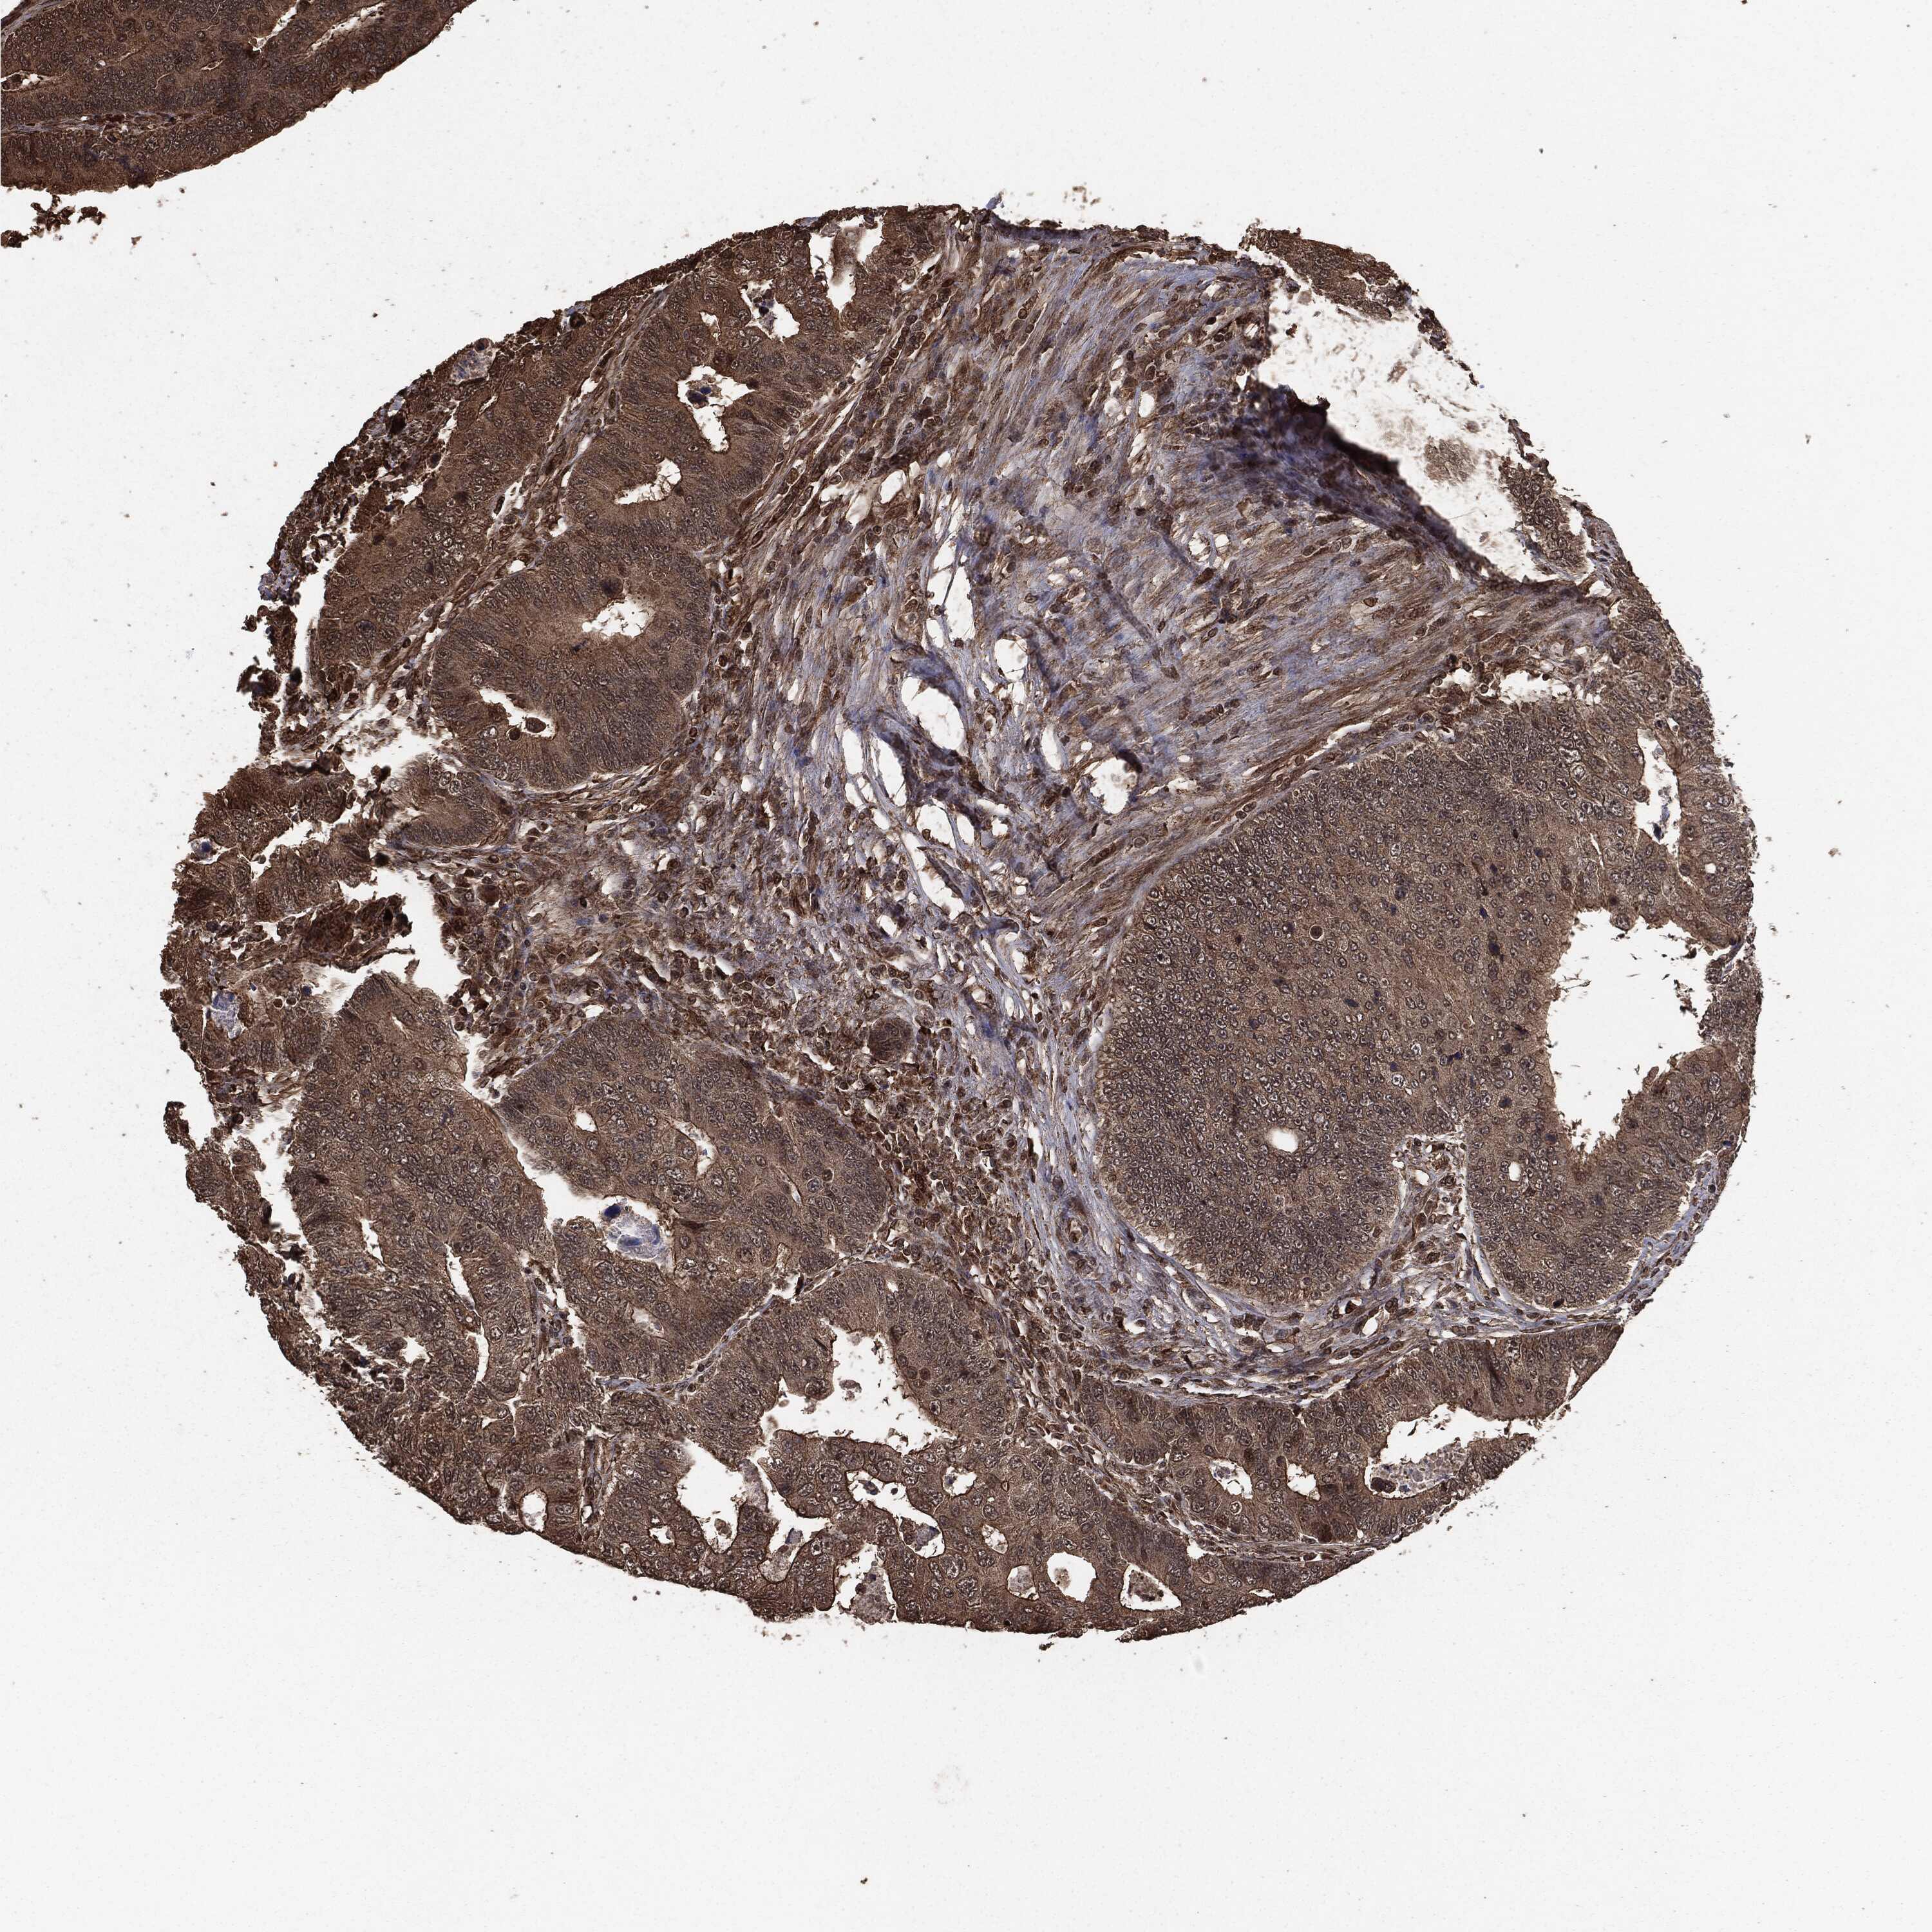

CANCER COLORECTAL CANCER Show tissue menu

Colorectal cancer

Human cancer

Colon adenocarcinoma